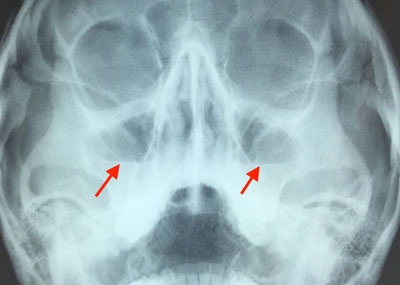

Исследование рентгеном является эффективным методом диагностики состояния околоносовых пазух.

Врач-отоларинголог назначает диагностику и лечение. Он осматривает нос, проводит пальпацию пазух, выявляет болезненные участки и собирает анамнез. Основной метод диагностики — рентген придаточных пазух лица.

При воспалении пазух с нарушенной пневматизацией на рентгеновских снимках можно увидеть затемнения. Если пазухи заполнены гноем, это может привести к тотальному затемнению.

Определение степени пневматизации и выявление наличия патологических процессов возможно лишь путем анализа рентгеновского снимка.